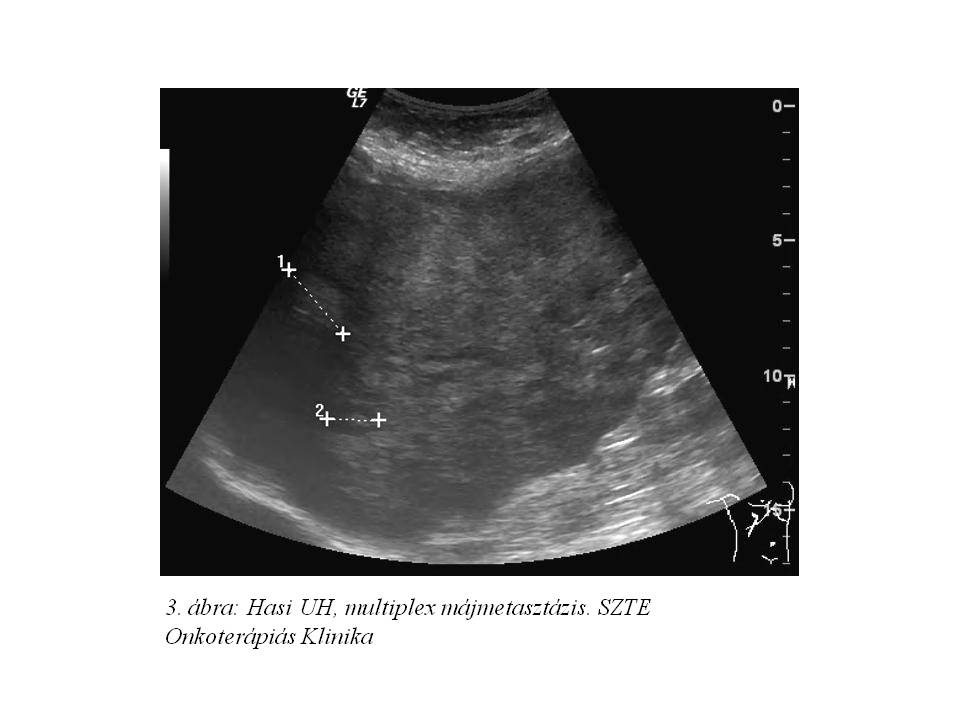

2013 októberében panaszai miatt sürgősséggel jelentkezett: étkezéstől függetlenül naponta többször hányt, hasa puffadt. Fizikális vizsgálattal hasa meteorisztikus, elődomborodó volt, hepatomegaliát tapintottunk. Laborvizsgálatban extrém hypercalcaemiát észleltünk, akut kezelésére intravénás zoledronsavat, forszírozott diurézist alkalmaztunk. Kivizsgálása során csont metasztázis nem igazolódott, azonban multiplex máj metasztázis igen (3. ábra), az emelkedett kalcium szint hátterében paraneoplasias szindrómát véleményeztünk. A kialakult progresszió miatt az adjuváns tamoxifén adását felfüggesztettük.